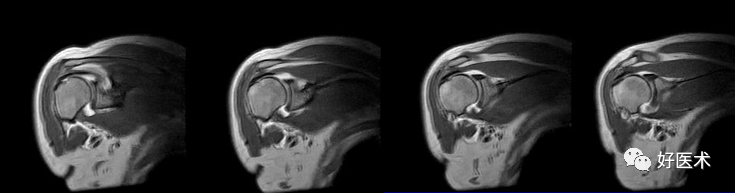

(2)扫描方位

横轴位:取三维立体定位像的冠状像,扫描层面与关节盂垂直,扫描范围从肩峰至肱骨颈下。

斜冠状位:取横断位作定位像,扫描层面与冈上肌腱平行,扫描范围为锁骨外端至肩峰。

斜矢状位:取横断位作定位像,扫描层面与关节盂平行,扫描范围包括肱骨头和整个关节盂。

斜冠状、斜矢状:显示肩袖及冈上肌走行、显示喙肩弓。

斜冠状、轴位:评估盂唇撕裂、肱二头肌长头腱与上盂唇的连接。